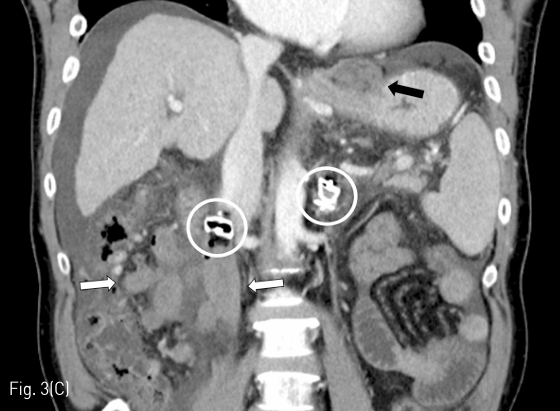

Fig 3A

(A-C) Contrast-enhanced CT images obtained 2 days after PARTO show complete thrombosis of gastric varices (black arrows) and mesenteric-retroperitoneal varices (white arrows). Arrow head indicates partial thrombosis of the SMV. White circles indicate plugs placed within the meso-caval shunt and the gastro-renal shunt.

Fig 3C